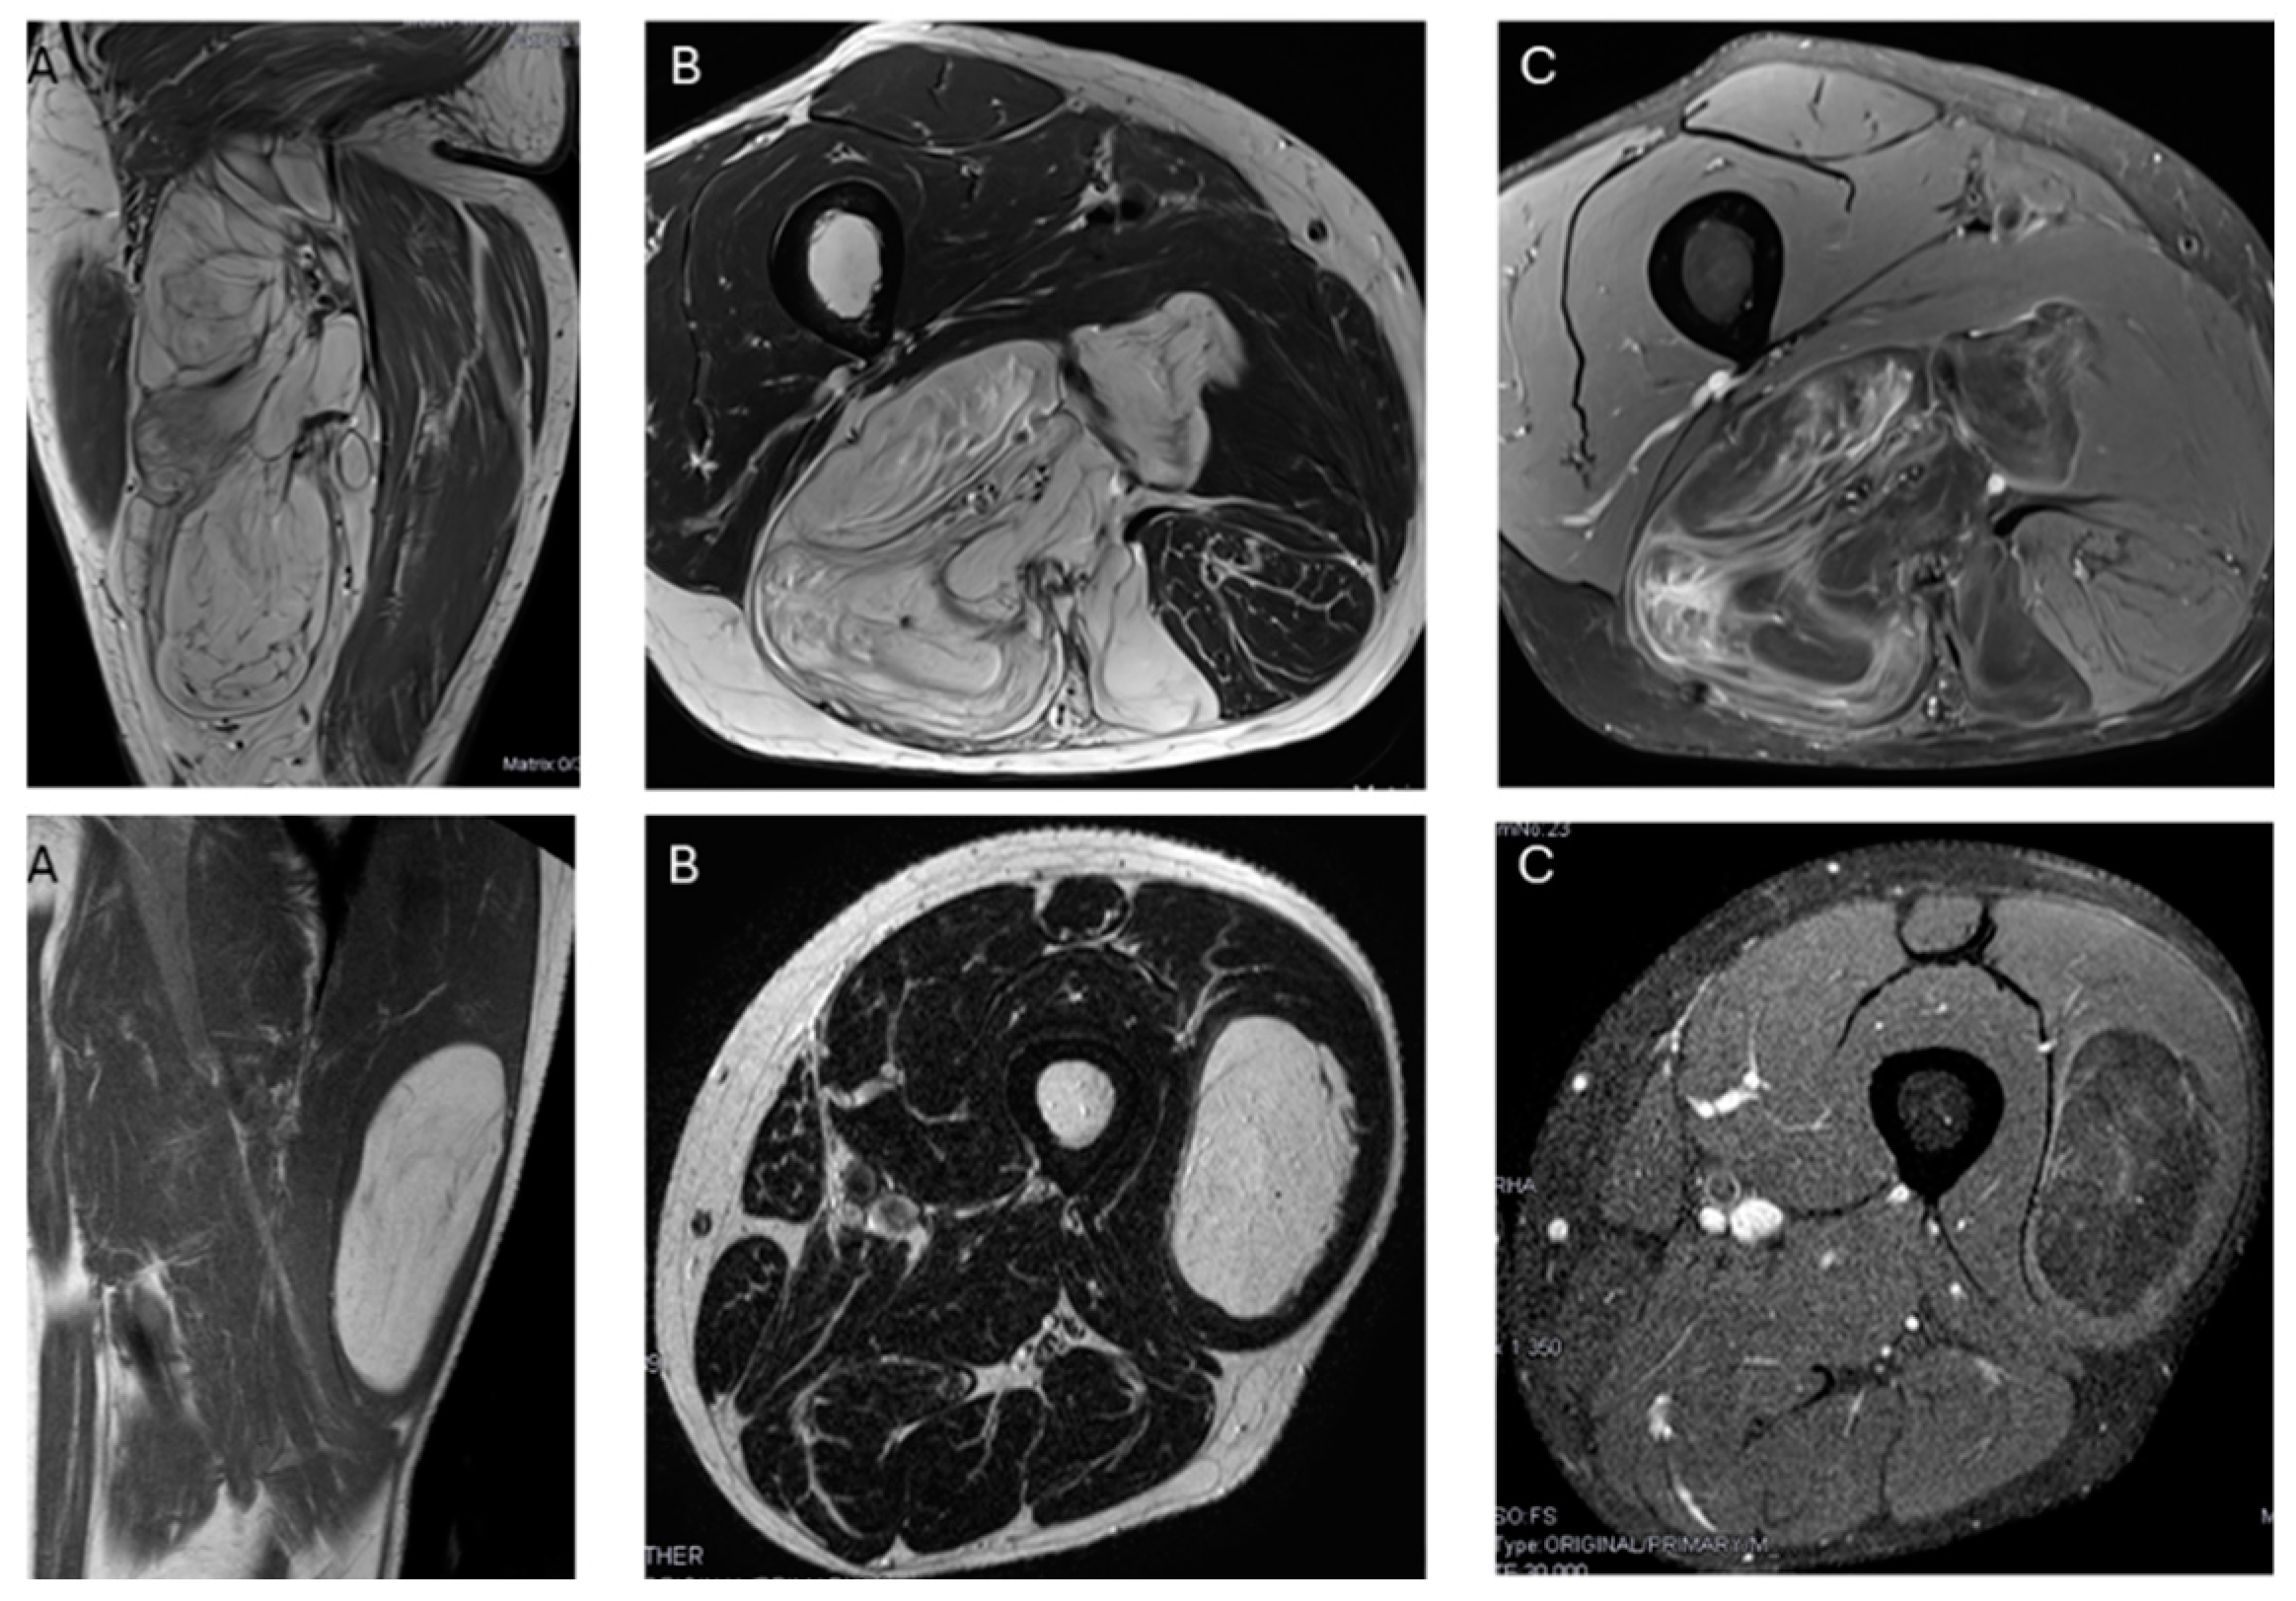

In our series, the lipomas showed both homogeneous and heterogenous fat signal intensity, while all ALTs were heterogenous tumors. Based on this criterion—the signal intensity of the tumor on MRI—some lipomas may be misinterpreted as ALT, but the opposite is not true; no ALTs would be misdiagnosed as a lipoma. With homogeneous hyperintensity on SE T1 and TSE T2 sequences, and complete suppression of the fat signal using fat suppression techniques, the diagnosis of lipoma can be made with high confidence. In contrast, heterogeneous tumors may be either a lipoma or an ALT (Figure 4) Therefore, homogeneous signal rules out ALT, while heterogeneous signal does not rule out lipoma (Figure 1).

Figure 4.

Top: Heterogeneous lipomatous mass in the posterior compartment of the thigh, measuring 22 cm, with multiple thick septa visible on T1 and T2 (A,B) and showing incomplete suppression on DP SPAIR (C). These MR findings are consistent with a radiological diagnosis of ALT. Final diagnosis: ALT (MDM2 positive). Bottom: Lipomatous tumor in the left lateral vastus, measuring 14 cm, with thin septa visible on T1 and T2 (A,B) and incomplete suppression on DP-SPAIR (C), leading to a radiological diagnosis of uncertain lipomatous tumor (lipoma versus ALT). Final diagnosis: lipoma (MDM2 negative).